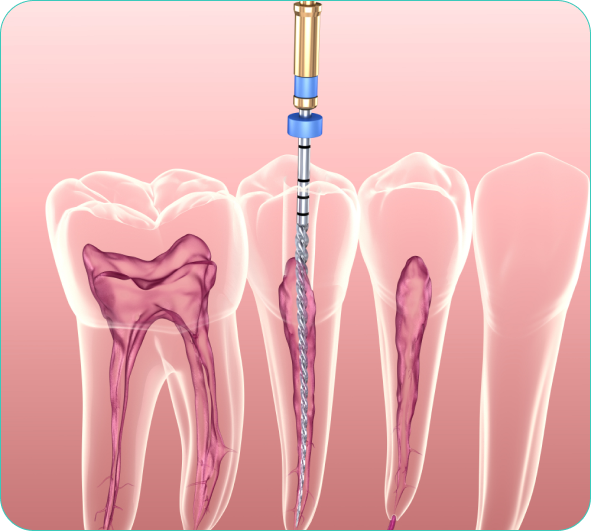

Every tooth is a three-layered structure namely – Enamel, Dentin & Pulp. If the tooth decay is limited to the first two layers, it can be corrected with Filling/ Restoration. In case the tooth decay reaches the third layer and causes inflammation or infection of pulp, an RCT or Endodontic Treatment is needed.We also provide Single Sitting Root Canal Treatment Using an advanced Endodontic technology Single-sitting Root Canal Treatment is performed within an hour. At Braces Faces Superspeciality dental care, dr.swapnil has performed more than 2000+ RCT with painless injection using modern equipment.Book appointment for painless single sitting RCT

At Braces & Faces Superspeciality Dental Care, Dr. Satyajit Has Done More Than 12,000+ Single Sitting Root Canal Treatment With Painless Technique & Latest Equipment.